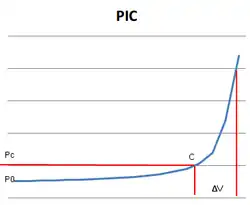

Alteraciones de la Presión intracraneal

Fisiológicamente, el SNC tiene una capacidad para amortiguar los cambios en la PIC (rango normal = 10mmHg ± 5mmHg) entre los que se incluyen la obliteración de las cisternas y ventrículos mediante la evacuación de líquido cefalorraquídeo (LCR) y la expulsión de hasta un 7% del volumen sanguíneo intracraneal fuera del lecho venoso cerebral.[28][29] Cuando la capacidad de regulación se agota, el paciente experimenta un aumento exponencial de su PIC (ver gráfico), lo cual ocurrirá de forma progresiva o de forma periódica. En este último caso habrá ascensos de 40-80 mmHg con una duración de 5 a 20 minutos. El aumento de la PIC reducirá la PPC por lo que inevitablemente se incrementará la isquemia cerebral preexistente y al no ser esta homogénea (por la compartamentalización de las meninges) la mayor magnitud de presión se localizará en las áreas donde exista una masa postraumática que se irá disipando mediante el desplazamiento del tejido cerebral llegando al enclavamiento.[5]